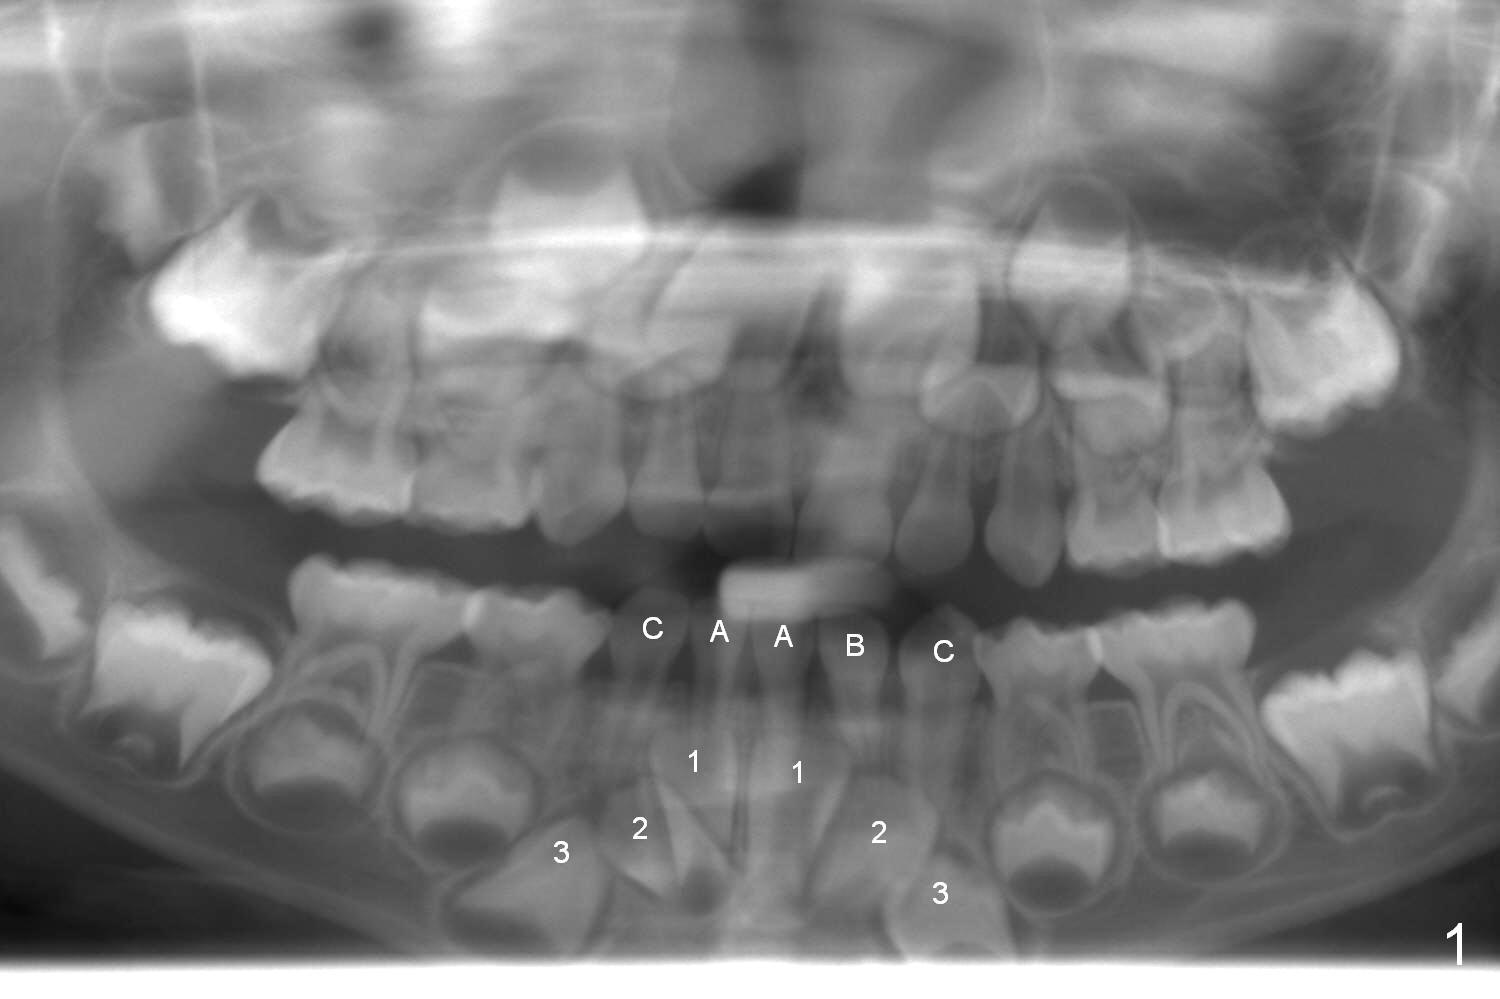

The lower right deciduous lateral incisor of a 5-year-old boy is congenitally missing (Fig.1). When he is 8 years old, the succedaneous tooth is unerupted (Fig.2). When the lower left canine (C) is exfoliated, extract LR C and LR 2 so that LR 3 has a chance to erupt normally.